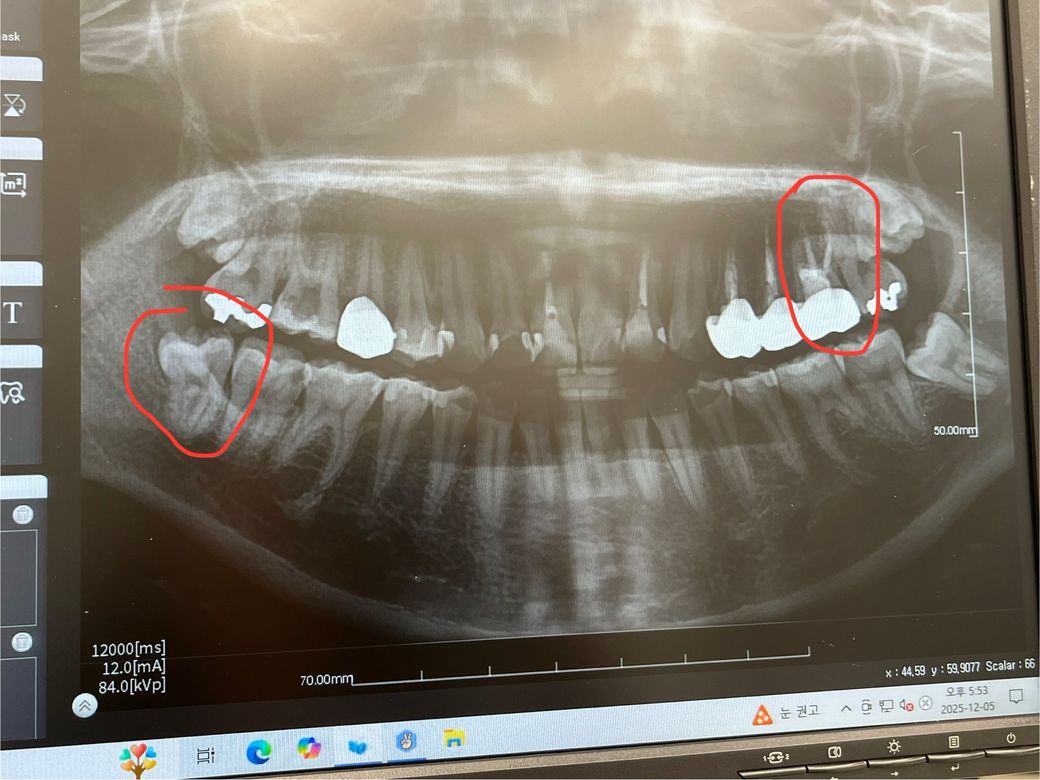

사랑니 발치하자고 하시는데 사랑니 이식술을 위해 사랑니 남겨둬도 될까요?

오른쪽 아래 맨 끝이 사랑니인데, 그 옆 치아를 신경치료해야 하거든요

옆 어금니 치료할 때 방해되기도 하고 장기적으로 봤을 때 빼는 게 좋다고 발치한 뒤 신경치료하자고 하셨거든요

근데 지금 왼쪽 위 신경치료 후 크라운 수복한 치아가 상태가 좀 불안불안해요 게다가 mta로 진행한 거라 잘못되면 발치해야 하거든요

나이가 어려서 인플란트만큼은 피하고 싶어서 찾아보다가 사랑니 이식술이라는 걸 알게됐는데 해당 사랑니 혹시 모르니 살려두는 게 좋을까요?ㅠ 의사쌤한테 말씀드려봐도 될까요..

사랑니를 이용한 치아 이식술은 치과에 따라 하고 못하고가 아니고 사랑니 상태가 좋아야 합니다. 발치 할 때 아무 손상 없이 발치가 되어야 하는데 현재 그런 상태의 사랑니가 아닙니다.